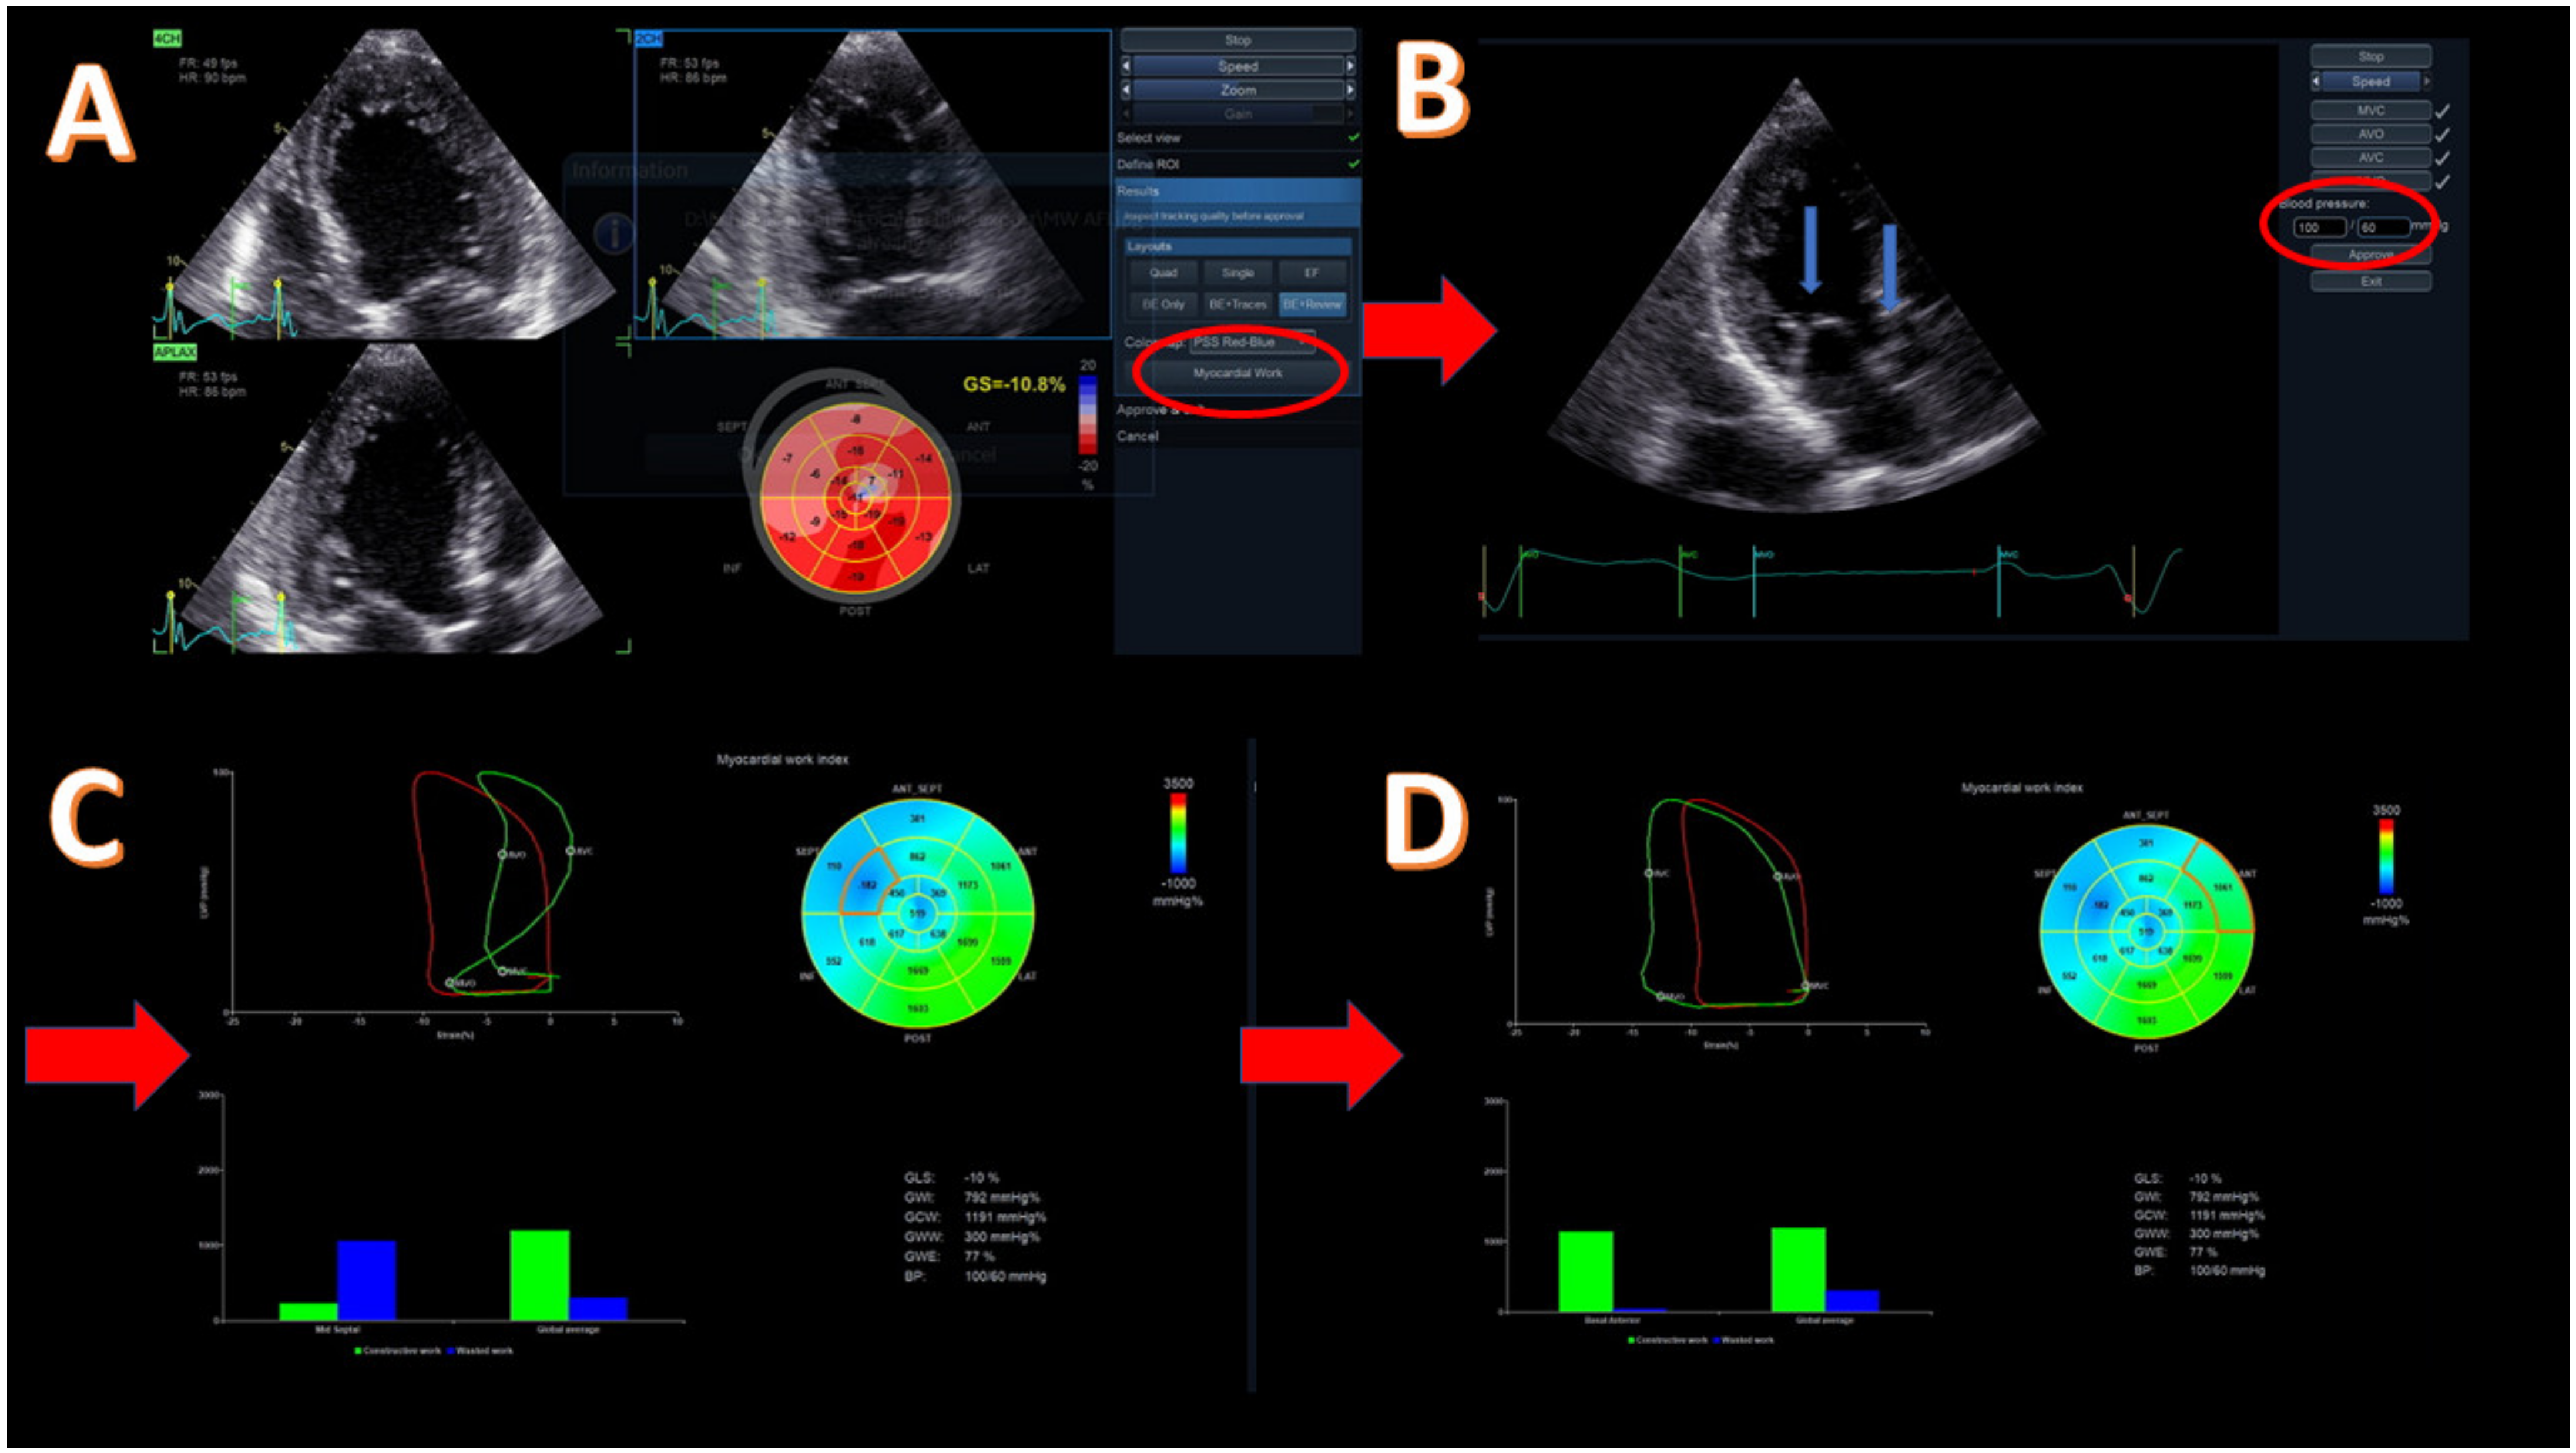

Methodology of myocardial work (MW) for a patient with reduced ejection fraction (EF = 30%) due to cardiotoxicity. (A) Acquisition of apical four-, two-, and three-chamber view and evaluation of global longitudinal strain (GLS) with left ventricular (LV) bull’s eye; GLS = −10.8%. The highlighted button (with red circle) moves to the next step for myocardial work evaluation. (B) Introduction of systolic and diastolic blood pressure (red circle) and confirmation of the correct event timing in apical three-chamber view. The blue arrows point to mitral and aortic valves that should be clearly demonstrated. (C) Evaluation of global values of all MW components, including bull’s eye of the work index, global pressure–strain loop (red loop), and segmental pressure–strain loop (green loop), showing a dyssynchronous mid-septum segment and bars showing the relationship between the constructive (green bar) and wasted (blue bar) segmental (left) and global work. (D) Evaluation of the same global values as in image C but with different segment for pressure–strain loop analysis and with constructive/wasted work bars. Basal anterior segment with constructive work similar to the global one. Red arrows show the next step of the methodology.